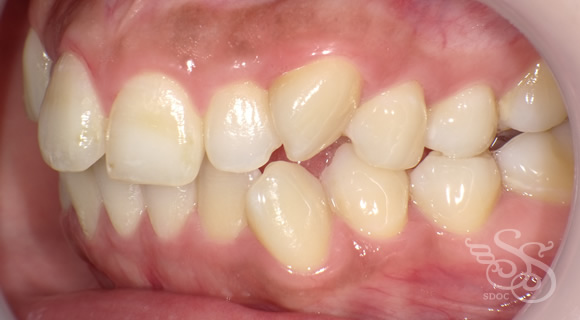

右側:術前

右側:術後

左側:術前

左側:術後